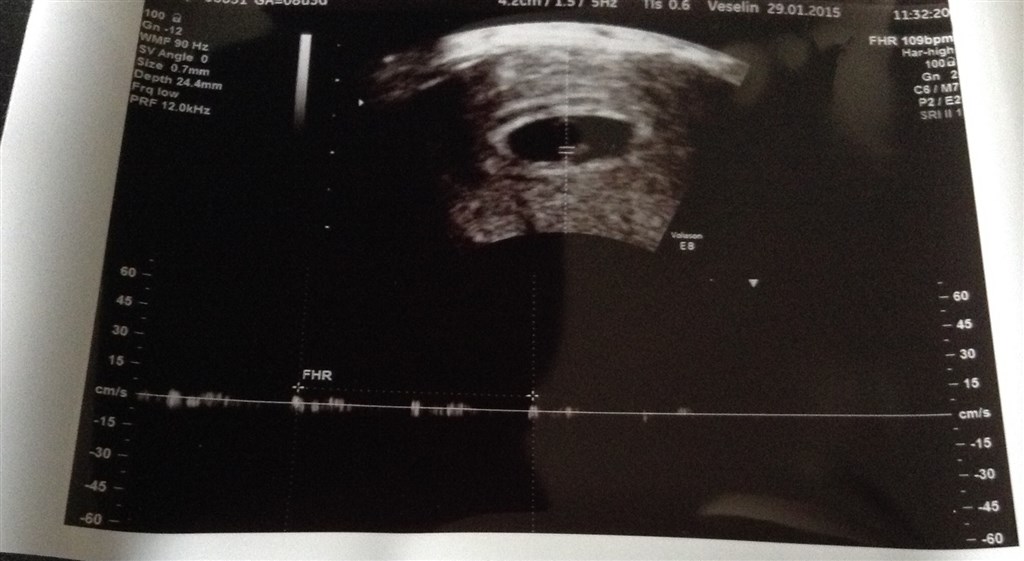

Jeg har været til scanning og var kun 6+1 men så hjerteblik. Og det var dejligt bare at blive bekræftet i at man faktisk er gravid ! troede dog at jeg har 7-8,5 uger henne. Men hørte også hjertelyd!

Men det er dog ikke meget man kan se på billederne andet end en lille klump hehe

Vedhæftede fotos (klik for at se i fuld størrelse)